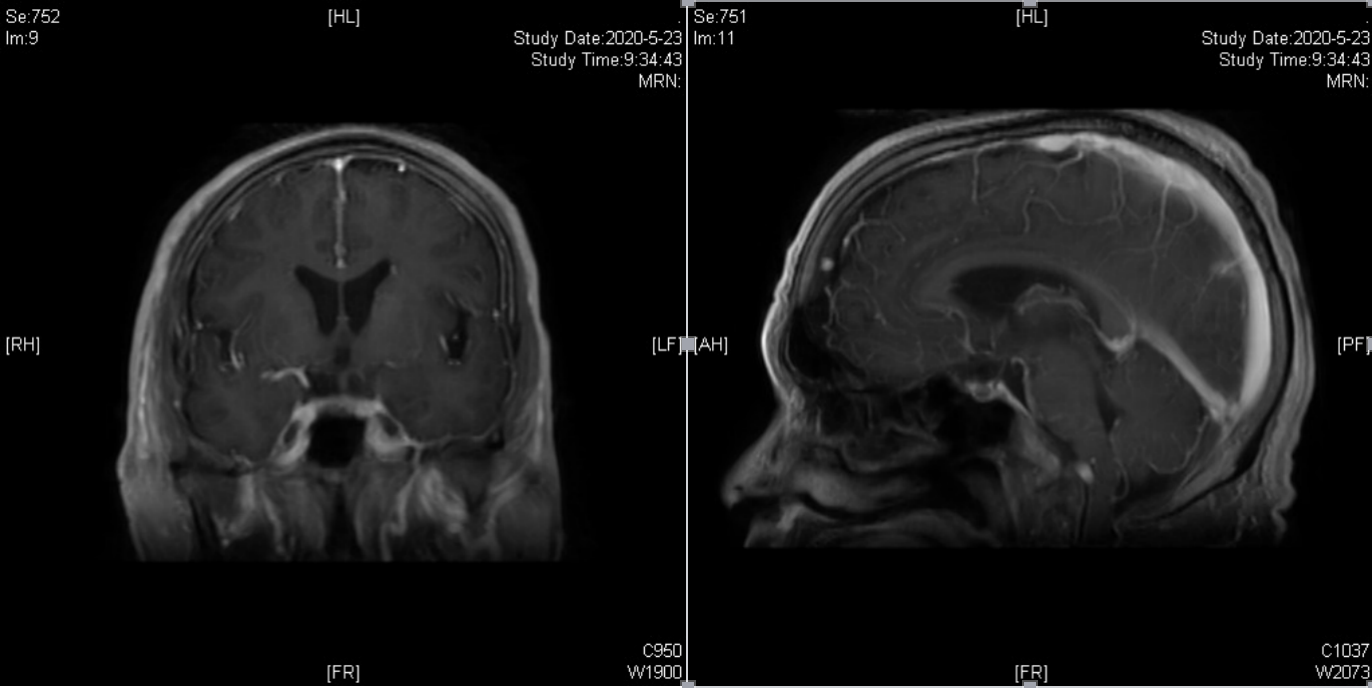

切口与体位

术前留置腰大池,取右侧眶外侧入路,切口长约10cm,铣下约6*4cm骨瓣。